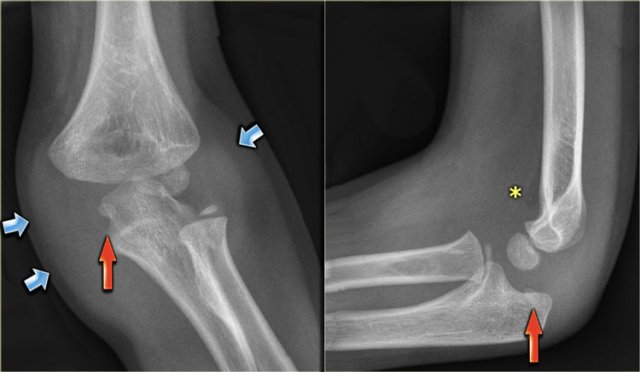

There is a 50% incidence of associated elbow dislocations.

When the elbow is dislocated and the medial epicondyle is avulsed,

it may become interposed between the articular surface of the humerus and the olecranon (figure).

In every dislocation the first question should be 'where is the medial epicondyle'.

On reducing the elbow the fragment may return to it's original position or remain trapped in the joint.

This may severely damage the articular surface.

So post-reduction films should be studied carefully.

Study the images.

You can click on the image to enlarge.

There are three findings, that you should comment on.

- There is enormous soft tissue swelling, which indicates that the elbow has been dislocated (blue arrows). So the next question is where is the medial epicondyle?

- The medial epicondyle is seen entrapped within the joint (red arrows).

- Notice that there is only minor joint effusion (asterix). The medial epicondyle is an extra-articular structure and avulsion will not produce joint effusion. The small amount of joint effusion is probably the result of the prior dislocation.

Continue with the MRI.

The MR shows the small medial epicondyle with tendon attachement trapped within the joint.

The avulsed medial epicondyl was found within the joint and repositioned and fixated with K-wires.